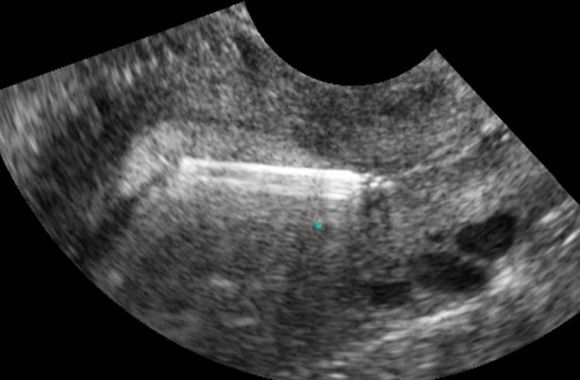

Современные экспертные УЗИ сканеры дают возможность проводить исследования всех органов в 3D. Это позволяет, используя полученный массив данных, получать диагностические сечения в любой плоскости, недоступной для обычного 2D УЗИ. Наиболее интересной является фронтальная. Например, визуализация полости матки. Диагностическая возможность выявления пороков развития превосходит все другие методы (рентгеновские и МРТ). Метод также позволяет уточнить положение ВМК (спирали) в полости матки, расположение миоматозных узлов, расположение плодного яйца на малых сроках, полипов. Сегодня современное экспертное ультразвуковое исследование невозможно без использования 3D УЗИ.